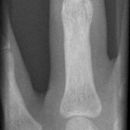

Bennett Fraktur mit geringer Dislokation